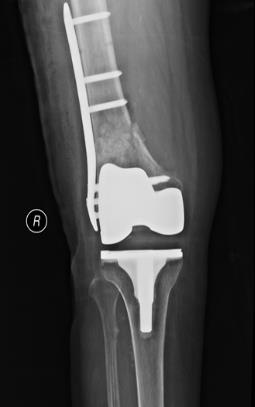

(六)膝关节置换术后假体周围骨折内固定术